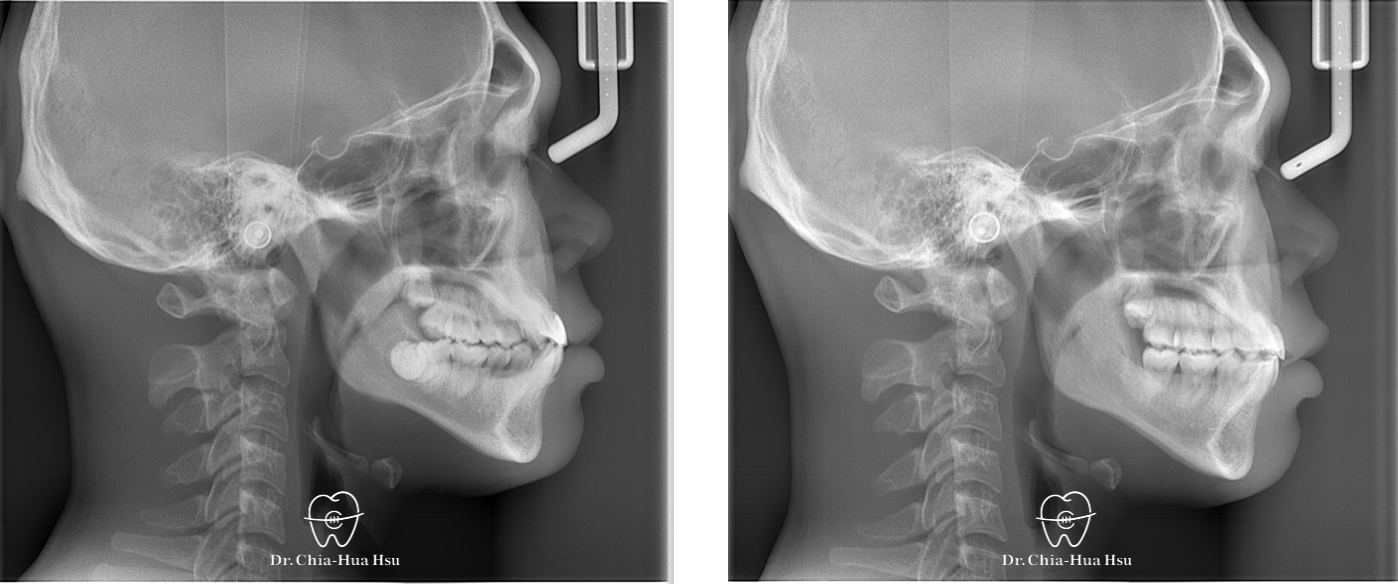

前牙錯咬、齒列擁擠

• 問題分析:患者是標準的骨骼一類咬合(Skeletal Class I)伴隨齒列擁擠以及前牙錯咬。

• 治療方式:拔除四顆小臼齒,使用傳統金屬矯正器將牙齒排列整齊、咬合緊閉。

治療前

治療後